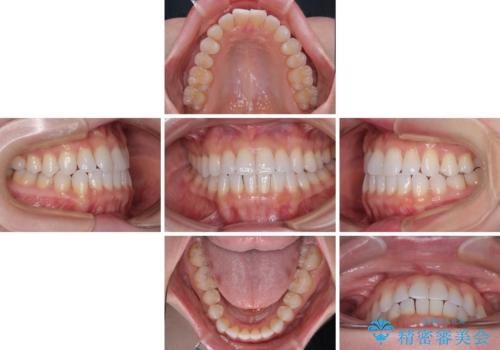

- 上下前歯の叢生を気にして来院された患者様です。

インビザラインでの治療を希望されていて、デコボコの程度が中等度であり、安価なパッケージにて対応可能と判断されたため、インビザライン・モデレートを用いて矯正治療を行うこととしました。

インビザライン・モデレートは、製作できるアライナーの枚数に制限があるため、移動可能な量に限りがあるものの、インビザライン・ライトよりも枚数が多いため、幅広い症例に対応可能です。